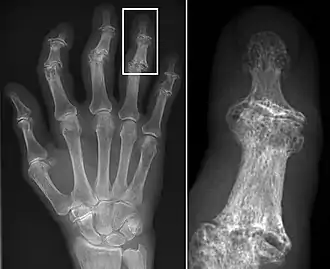

Osteoarthritis (OA) is a degenerative joint disease that affects the junctions of articulating elements, or synovial joints (e.g. knee, shoulder) and is characterized by the damage of cartilage. OA is the most commonly documented pathology found in archaeological human remains and has been used extensively as an activity marker that reflects stress-related activity patterns or occupation.[11] Factors such as age, sex, body size and others also affect its expression.[12]

Sherry Fox from the Arizona State University, and her colleagues, explored traumatic patterns from different Early Christian church/basilica sites in Cyprus: Agios Georgios Hill, Nicosia, Kalavasos-Kopetra, Alassa-Ayia Mavri, and Maroni-Petrera. The Hill of Agios Georgios is situated inland adjacent to the Pediaios River outside the Venetian walled city of Nicosia, while the rest of the sites are located near the south coast. The aim of the study was to identify trauma patterns between the smaller, coastal sites and the larger, inland site. Trauma patterns, attributed to demographic differences, were evident between the inland and coastal sites, with a higher prevalence attested at the inland site of the Hill of Agios Georgios. A second difference was that males at the Hill of Agios Georgios had a higher propensity for traumatic lesions in the upper body and hand extremities, and this has been suggested to be caused by reasons beyond demographic parameters. The authors suggest that additional factors such as cultural, behavioral, and/or occupational differences, may account for the differences observed between the inland and coastal sites.[26]